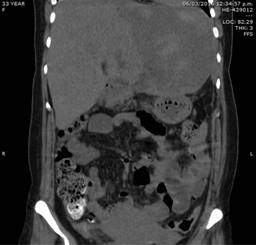

La paciente es trasladada a la Unidad de Cuidados Intensivos estable con presión arterial media de 70 mmHg, se realiza desempaquetamiento hepático a las 48 horas sin evidencia de sangrado activo, apreciándose hígado con adecuada consistencia, coloración, turgencia y con hematoma limitado (Figura 2). Veinticuatro horas después se retira el apoyo ventilatorio mecánico sin complicaciones, presentando adecuada evolución con tolerancia de la dieta, drenajes sin evidencia de sangrado activo; los exámenes de laboratorio a los siete días con hemoglobina de 11 g/dl, plaquetas de 332,000 y tiempos de coagulación dentro de parámetros normales, pruebas de funcionamiento hepático dentro de parámetros normales. Es egresada de la Unidad de Cuidados Intensivos estable, a los nueve días del postoperatorio presenta fiebre persistente, se realiza control tomográfico localizando amplia zona de necrosis en lóbulo hepático izquierdo y hematoma intraparenquimatoso de 15 x 10 centímetros (Figura 3), motivo por el cual se realiza nueva laparotomía exploradora con hallazgo de lóbulo hepático izquierdo necrótico y hematoma extenso de 1,500 ml (Figura 4); se realiza evacuación del hematoma, hepatectomía izquierda (Figura 5).

Figura 3: Control tomográfico a los nueve días con datos de necrosis en lóbulo hepático izquierdo y hematoma intraparenquimatoso de 15 x 10 centímetros.